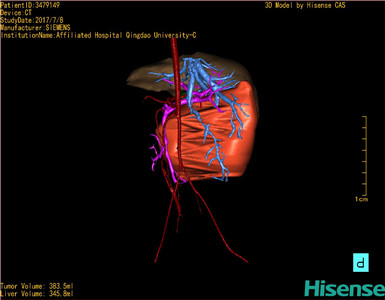

将0.625mm双源薄层CT资料的静脉期和动脉期Dicom格式文件导入海信CAS系统。

通过调节窗宽窗位调整CT序号,对肝实质,胆囊,下腔静脉,肿瘤,肝动脉、门静脉及肝静脉等进行三维重建;系统自动计算肝脏体积。

模拟手术操作,自动计算切除肿瘤体积。肝脏体积为345.8ml,肿瘤体积383.5ml,是肝脏体积的1.1倍,通过比对6-9月岁正常肝脏体积为257.75±51.05ml,通过术前模拟手术,精准判断切除后剩余肝脏体积能耐受,避免肝衰竭发生。

术前三维重建:

重建图片